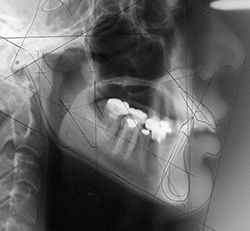

骨格と筋肉の関係を考えて、様々な矯正装置を選択し、容貌全体のバランスを整えて1㎜ずつ歯列を整えていきます。

正常な咬み合わせになるよう、顔の歪み、歯の向き、角度、大きさを揃えていきます。

一般の歯科医院にはない、矯正歯科用の特別なレントゲンで、頭を基準にして歯の傾き、上下の顎骨の位置関係や歯列の形態や位置に関する特徴や成長を評価し、理想の歯並びになるように診査診断を行います。